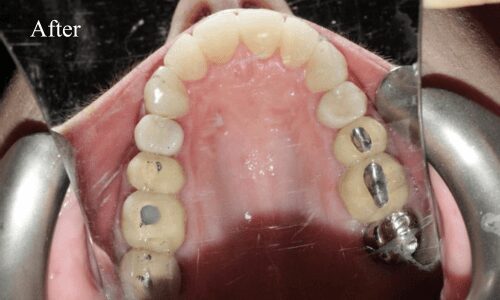

Dental Bridges

Dental bridges are also known as dental restorations and are comprised mainly of dental crowns which are attached to the sides of the abutment tooth. The dental crowns blend in perfectly with the abutment teeth and bridge the gap resulting in a natural appearance. The greatest advantage of using these dental bridges is their durability. They can last for many years if properly cared for.

Dental Crowns

A dental crown procedure is a rather simple dental treatment but one that requires a great deal of precision and expertise. All our procedures begin with an in-depth consultation.

Next, a cast of the patient’s teeth is taken to develop dental crowns perfectly customized according to the patient’s unique dental and bone structure. We want the dental crown to cover the affected tooth/teeth completely and blend naturally with the rest of the teeth. After the first appointment with us at our Katy dental clinic, the patient may be provided with temporary crowns until the time their final dental crowns are ready.

During a second appointment, the final and permanent dental crowns are capped over the affected teeth to cover them completely and are bonded with the help of a dental adhesive. We will use a local anesthetic at this stage if needed. Our Katy dental specialists ensure the dental crown process is fast, safe and pain free.